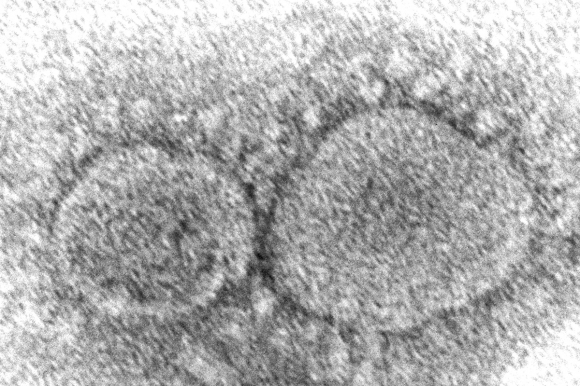

| 미국 질병통제예방센터(CDC)가 전자현미경으로 촬영한 코로나19 바이러스. CDC 제공 |